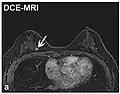

Dynamic contrast enhanced DCE Measures changes over time in the shortening of the spin–lattice relaxation (T1) induced by a gadolinium contrast bolus.[90] Faster Gd contrast uptake along with other features is suggestive of malignancy (pictured).[91]

(VIPR)